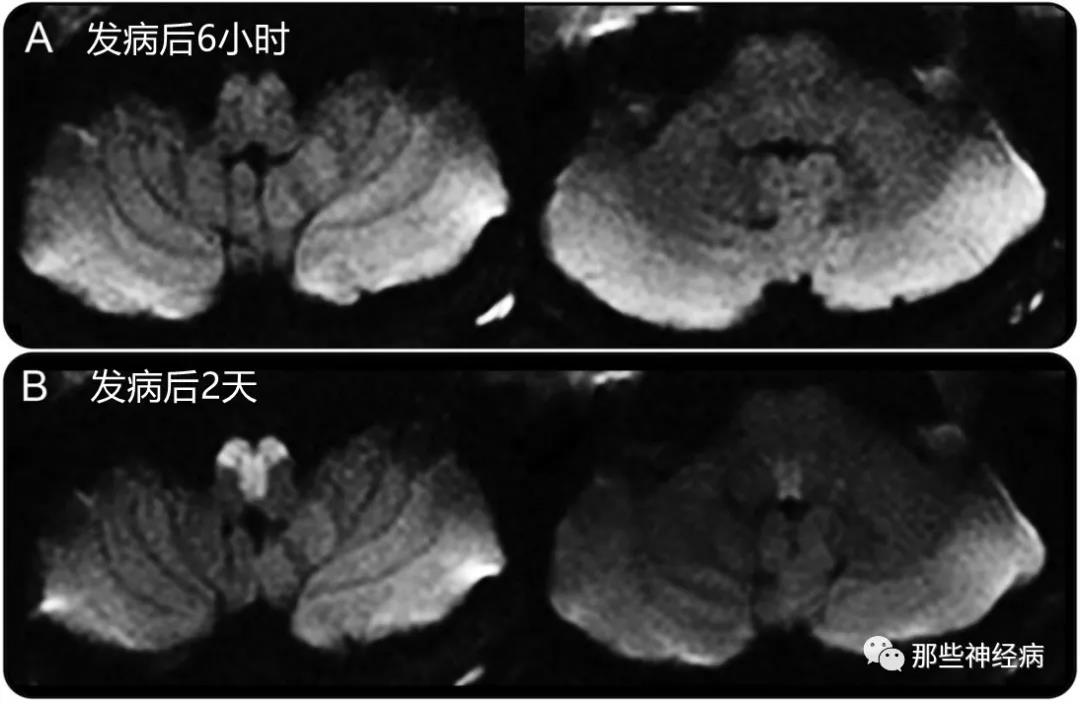

患者当晚病情加重,出现头晕、右侧肢体肌力从4级下降至2级,复查头颅CT无出血,立即予以替罗非班治疗,但病情持续性加重,并出现呼吸困难,四肢瘫痪(右侧肢体肌力0级,左侧肢体肌力2级),行气管插管、使用有创呼吸机辅助通气,次日复查头颅DWI,病灶扩大,并进展为双侧: